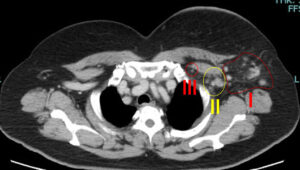

他院、初診時のCT

皮膚肥厚を伴う大きな腫瘍

リンパ節転移も腋窩(Ⅰ+Ⅱ)鎖骨下(Ⅲ)

両方に著明

前医で「手術不能乳癌、薬物療法しかできない」と、言われ当院を受診

注1)(我々は)フェスゴ+DTXx4クールでoperative(手術可能)になるとは考えにくいと考えていること

→実際に手術可能となったわけだけど…

それでも私は全摘+腋窩鎖骨下郭清しています。

この部分は(実は)彼らの「技術レベルの低さ」を露呈しているのではないか?と思っている。

そもそも「鎖骨下に転移がある」時点で、(自分たちの手に負えない)=手術できない(しても仕方がない)としか見ていないように思う。